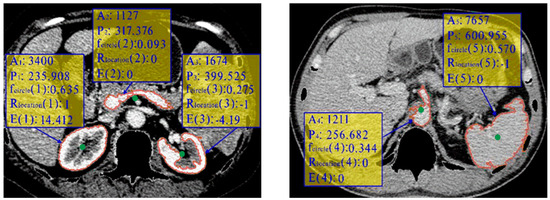

Kidney segmentation from abdominal computed tomography (CT) images is essential for computer-aided kidney diagnosis, pathology detection, and surgical planning. This paper introduces a kidney segmentation method for clinical contrast-enhanced CT images. First, it begins with shape-based preprocessing to remove the spine and ribs. [...] Read more.

Kidney segmentation from abdominal computed tomography (CT) images is essential for computer-aided kidney diagnosis, pathology detection, and surgical planning. This paper introduces a kidney segmentation method for clinical contrast-enhanced CT images. First, it begins with shape-based preprocessing to remove the spine and ribs. Second, a novel clustering algorithm and an initial kidney selection strategy are utilized to locate the initial slices and contours. Finally, an adaptive narrow-band approach based on active contours is developed, followed by a clustering postprocessing to address issues with concave parts. Experimental results demonstrate the high segmentation performance of the proposed method, achieving a Dice Similarity Coefficient of 97.4 ± 1.0% and an Average Symmetric Surface Distance of 0.5 ± 0.2 mm across twenty sequences. Notably, this method eliminates the need for manually setting initial contours and can handle intensity inhomogeneity and varying kidney shapes without extensive training or statistical modeling. Full article